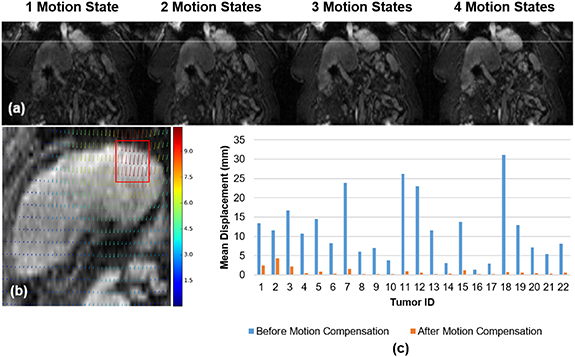

3.3. Tumor tracking

Figure 9(a) compares the diaphragm boundary deformation between the 4 motion states of the XD-GRASP reconstructed image. The diaphragm boundaries are marked by the white line. The results show that there is a clear motion between different phases which was confirmed by the deformation vector field between the first and last motion state represented in figure 9(b).

Figure 9. (a) Comparison of diaphragm position between motion states. (b) Deformation vector field (in pixel) for a sample case between the first and last phases (tumor identified by red box). (c) Tumors displacement (mm) before and after motion compensation.

Download figure:

Standard image High-resolution imageThe mean Euclidean distance calculated before registration for each tumor varies between 1.3 mm to 31 mm (mean 11.9 ± 8 mm) depending on the respiration of each patient as shown by the blue bars in figure 9(c). Following motion compensation, tumor target displacements varied between 0.2 and 4 mm (mean 0.9 ± 1 mm), as shown by the orange bars in figure 9(c).